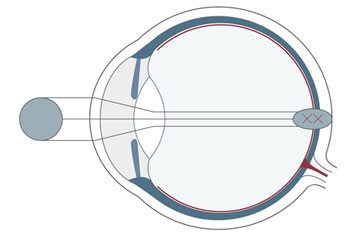

Wer unscharf sieht, war bisher gezwungen, sich mit Brillen und Kontaktlinsen zu behelfen. Die Refraktive Chirurgie ist mit dem LASIK-Verfahren in der Lage, die Sehschwäche am Auge selbst zu korrigieren. Das LASIK-Verfahren hat sich als die erfolgreichste und weltweit am häufigsten angewandte Methode zum Augenlasern etabliert.

Bei Kurzsichtigkeit, Weitsichtigkeit und Alterssichtigkeit sowie bei einer Hornhautverkrümmung setzen wir einen Augenlaser ein, der sich auf dem allerneuesten Stand der Technik befindet. Das Augenlasern führen wir ambulant durch, der Eingriff selbst dauert nur wenige Minuten. Welche Methode beim Augenlasern zum Einsatz kommt, wie sich der Ablauf beim genau gestaltet und welche Kosten hierdurch entstehen, ist abhängig von der vorliegenden Fehlsichtigkeit.